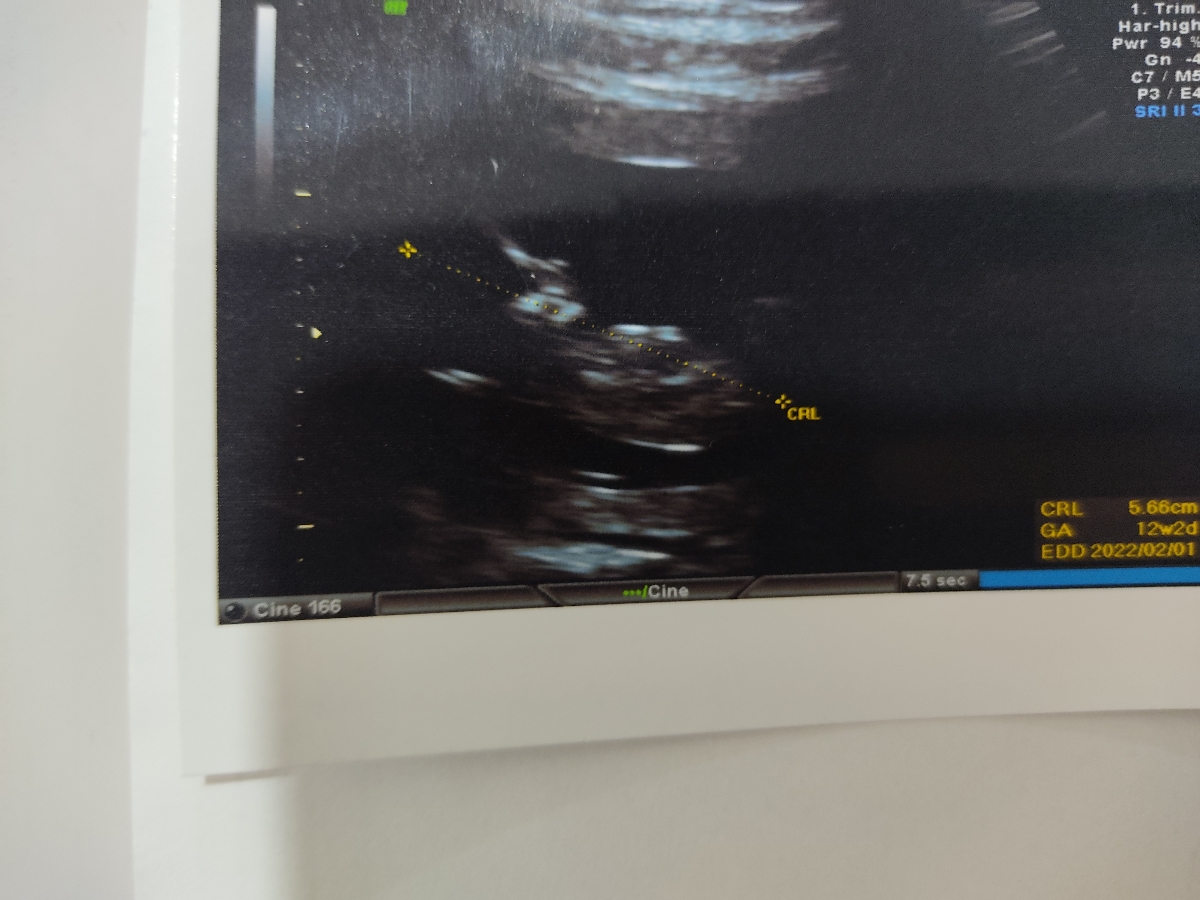

الان ۱۳ هفتمه دوهفته دیگ میشه ۱۵ دیگ

الان دقیقا ۱۳ هفته و چند روزی؟

۱۳ هفته یک روزمه

دو هفته دیگه برو جنسیت منم ۱۲ ام میرم تعیین جنسیت

خماری خوب نیست من ۱۳ هفته و ۵ روزم